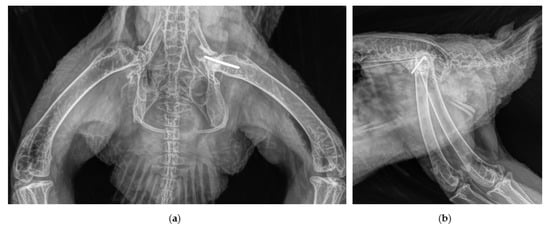

2.2. Surgical Procedure and Post-Surgery Management